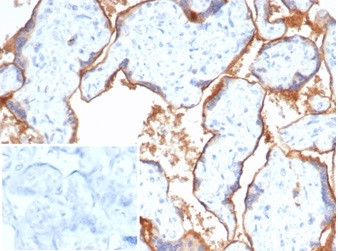

Nectin 4/Nectin Cell Adhesion Molecule 4/PVRL4 Antibody in Immunohistochemistry (Paraffin) (IHC (P))

Nectin 4/Nectin Cell Adhesion Molecule 4/PVRL4 Antibody (81607-MSM1-P1ABX) in IHC (P)

Formalin-fixed, paraffin-embedded human placenta stained with NECTIN4 Mouse Monoclonal Antibody (NECT4/7271). Inset: PBS instead of primary antibody; secondary only negative control. {{ $ctrl.currentElement.advancedVerification.fullName }} 验证信息 View more